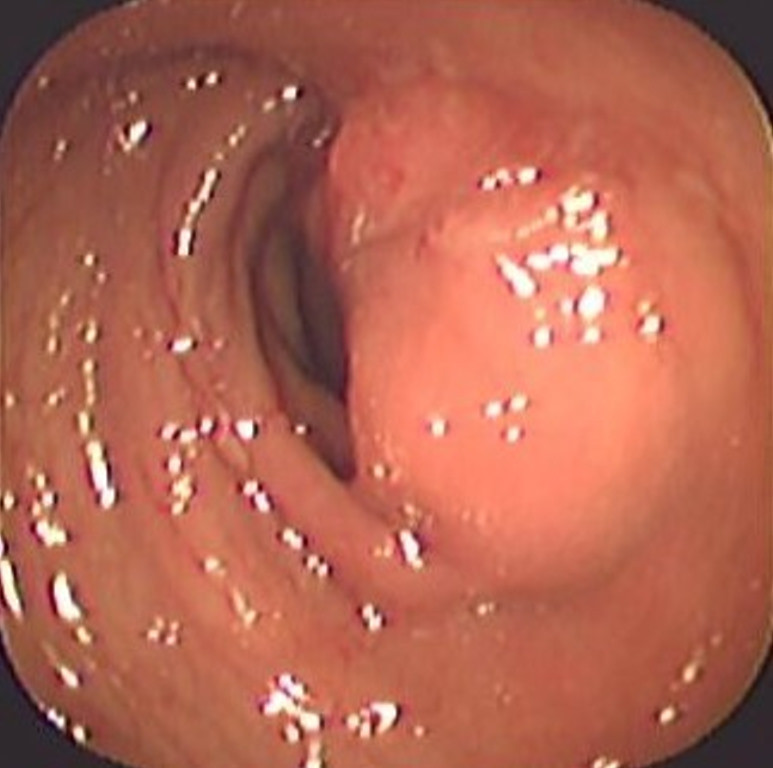

Cáncer de Colon

Envíado por Dr. Carlos Ernesto Arévalo